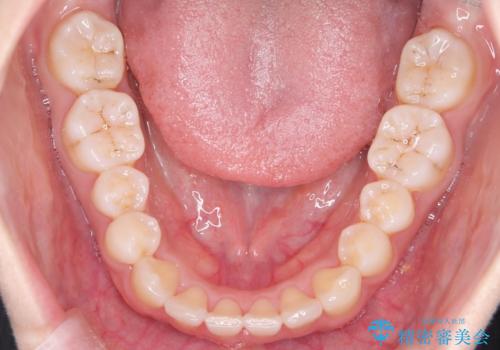

【インビザライン】八重歯が気になる

- 乳歯を抜歯してスペースを確保し八重歯の改善を行いました。

インビザラインをしっかり使用していただいたので、きれいな歯並びになりました。